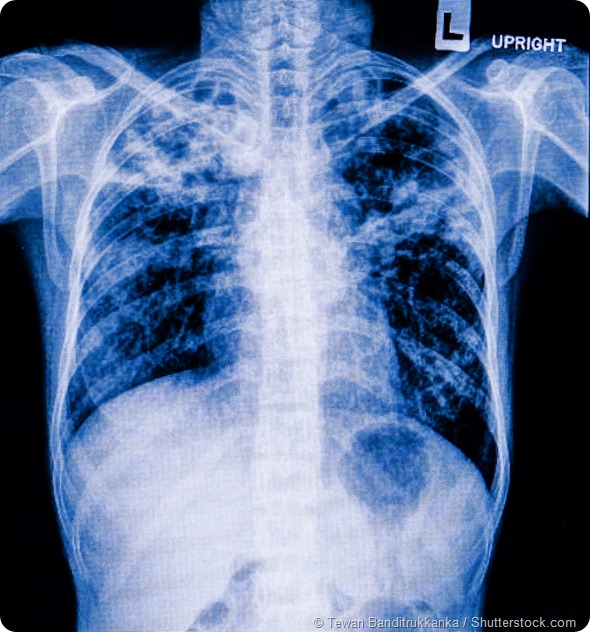

Can you give me a brief overview of bacterial lung infections and why they are so lethal?

When scientists first started to look at what happened during the 1918-1919 pandemic, what we saw was that the major cause of death was not the flu virus but that patients died due to a secondary bacterial pneumonia. So the major question became what was the 1918 flu strain doing that caused people to become susceptible to bacterial super-infections?

So scientists began digging patient samples from the Alaskan permafrost. What they observed was that the primary flu infection caused a significant amount of lung damage in the host without killing them, which then allowed streptococcus pneumonia, the common bacterial super infection, to grow in the lung and cause systemic infection. The body becomes unable to combat this bacterial super infection, which becomes the primary cause of mortality.